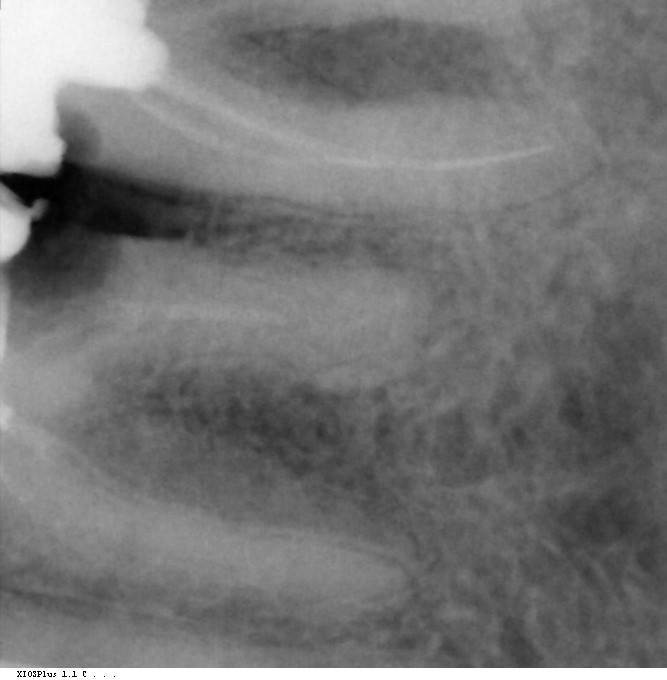

Marc Опубликовано 3 ноября, 2023 Поделиться Опубликовано 3 ноября, 2023 Добрый день. Возможно ли сделать что-то с такой 6-ой. Или никакой "Deep margin elevation" уже не поможет? Спасибо. Ссылка на комментарий

DoctorT Опубликовано 7 ноября, 2023 Поделиться Опубликовано 7 ноября, 2023 Здесь 5 нужно спасать, а не заботиться о трупе 6. Ссылка на комментарий

DoctorT Опубликовано 7 ноября, 2023 Поделиться Опубликовано 7 ноября, 2023 3 часа назад, red_butler сказал: 5 или 7й? 7 конечно, что то я невнимателный. Ссылка на комментарий

NazranDantist Опубликовано 10 ноября, 2023 Поделиться Опубликовано 10 ноября, 2023 Все зависит от врача. Классические показания говорят об удалении зубов, кариес корня - 100% удаление зуба по законодательству. Я бы даже не предлагал вам лечение, потому что не уверен в результатах, только удаление с имплантацией. Коллега же готов лечить и восстанавливать такие зубы. Поэтому вы должны для себя выбрать врача, довериться ему и следовать плану лечения. Ну и обговорить гарантийные обязательства клиники при том или ином плане лечения. Ссылка на комментарий